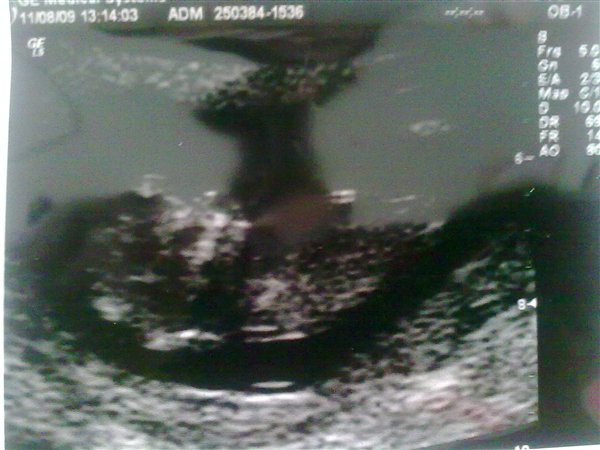

så fik vi taget NF. scan. idag med flotte resaulteter

1:18000 for downs

1:30000 for de 2 andre kromozonfejl de tjekker..

så rask og normalt barn.. eller så normalt som det kan blive med de 2 forældre

men en kæmpe oplevelse.. og se sit lille barn ligge der og bevæge sig.. det hele blev lige lidt mere virkeligt..